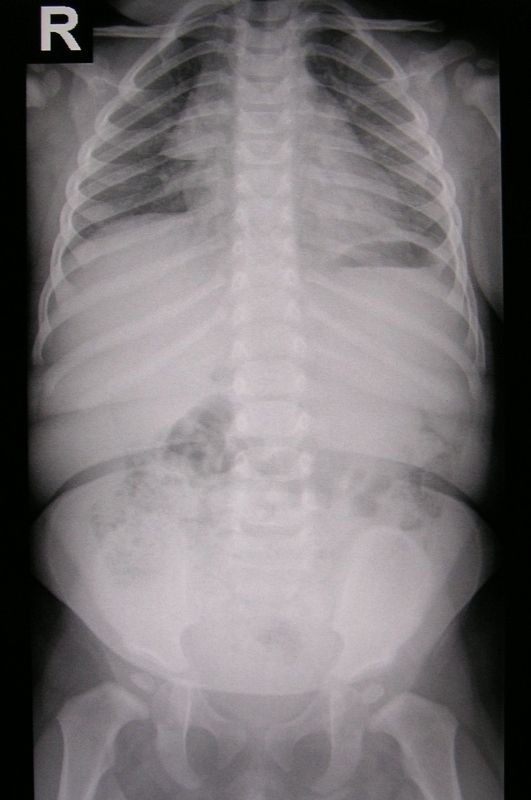

Plicní Embolie Rtg : Plicni Embolie Priciny Priznaky A Lecba Zdravi Euro Cz / Při zvažování diagnosy plicní embolie posuzujeme vedle klinických projevů přítomnost rizikových faktorů, laboratorní testy, ekg a rtg hrudníku.. Při zvažování diagnosy plicní embolie posuzujeme vedle klinických projevů přítomnost rizikových faktorů, laboratorní testy, ekg a rtg hrudníku. Ultrazvuk může zobrazit trombus v žilách dolních končetin, echokardiografické vyšetření může zobrazit přetížení pravé komory srdeční (v důsledku obstrukce plicnice).

Při zvažování diagnosy plicní embolie posuzujeme vedle klinických projevů přítomnost rizikových faktorů, laboratorní testy, ekg a rtg hrudníku. Ultrazvuk může zobrazit trombus v žilách dolních končetin, echokardiografické vyšetření může zobrazit přetížení pravé komory srdeční (v důsledku obstrukce plicnice).